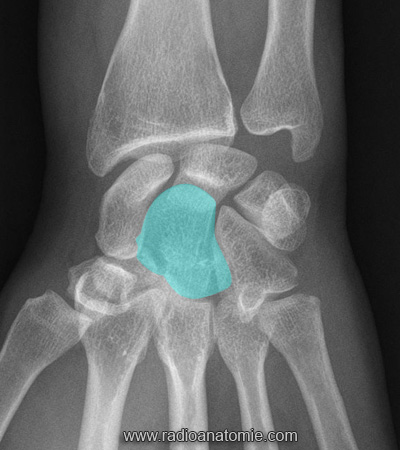

geopas Posté(e) 13 avril 2025 Signaler Posté(e) 13 avril 2025 En tapant "magnum rhinocerotidae" on tombe en effet sur quelques publications sérieuses en français utilisant le mot magnum qui est bien un os du carpe. Ce mot est-il utilisé dans l'anatomie humaine (c'est l'os capitatum) ou pas ? C'est le nouveau sous-Quizz du jour 😁 Citer

flachmat Posté(e) 19 avril 2025 Signaler Posté(e) 19 avril 2025 Le 13/04/2025 à 18:47, Mt Ventoux a dit : Pourtant ça figure dans des publis scientifiques françaises et anglaises. Donc peut être une synonymie moins utilisée ? https://www.radioanatomie.com/56_os_du_carpe/anatomie_os_du_carpe.php?vue=1&langue=it Les os du carpe (ancienne nomenclature ) Le Grand os = Le Magnum Citer